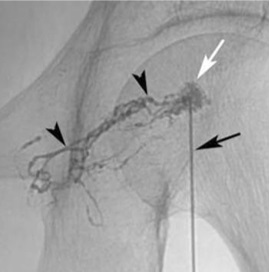

经皮乳糜池穿刺:胸导管入路 Thoracic Duct Access

2. 这新的淋巴管系统的可视化操作,增强了对淋巴流异常的认识,促进了创新介入技术的发展,包括胸导管外化、胸导管支架、淋巴结胶注射和经肝淋巴栓塞 淋巴介入的进展包括 经乳糜池入路栓塞和引流 间质淋巴管栓塞 Interstitial lymphatic embolization 经静脉胸导管导管术 TD catheterization 胸导管栓塞,不管是逆行还是顺行,目前技术已经成熟,文献超过100多例的报告。胸导管栓塞成功率(控制乳糜胸)80-90%,特别是使用液体栓塞剂。栓塞技术有一定难度(靶目标小、位于腹部深处、被穿刺的淋巴管触到针头可以任意移动)。